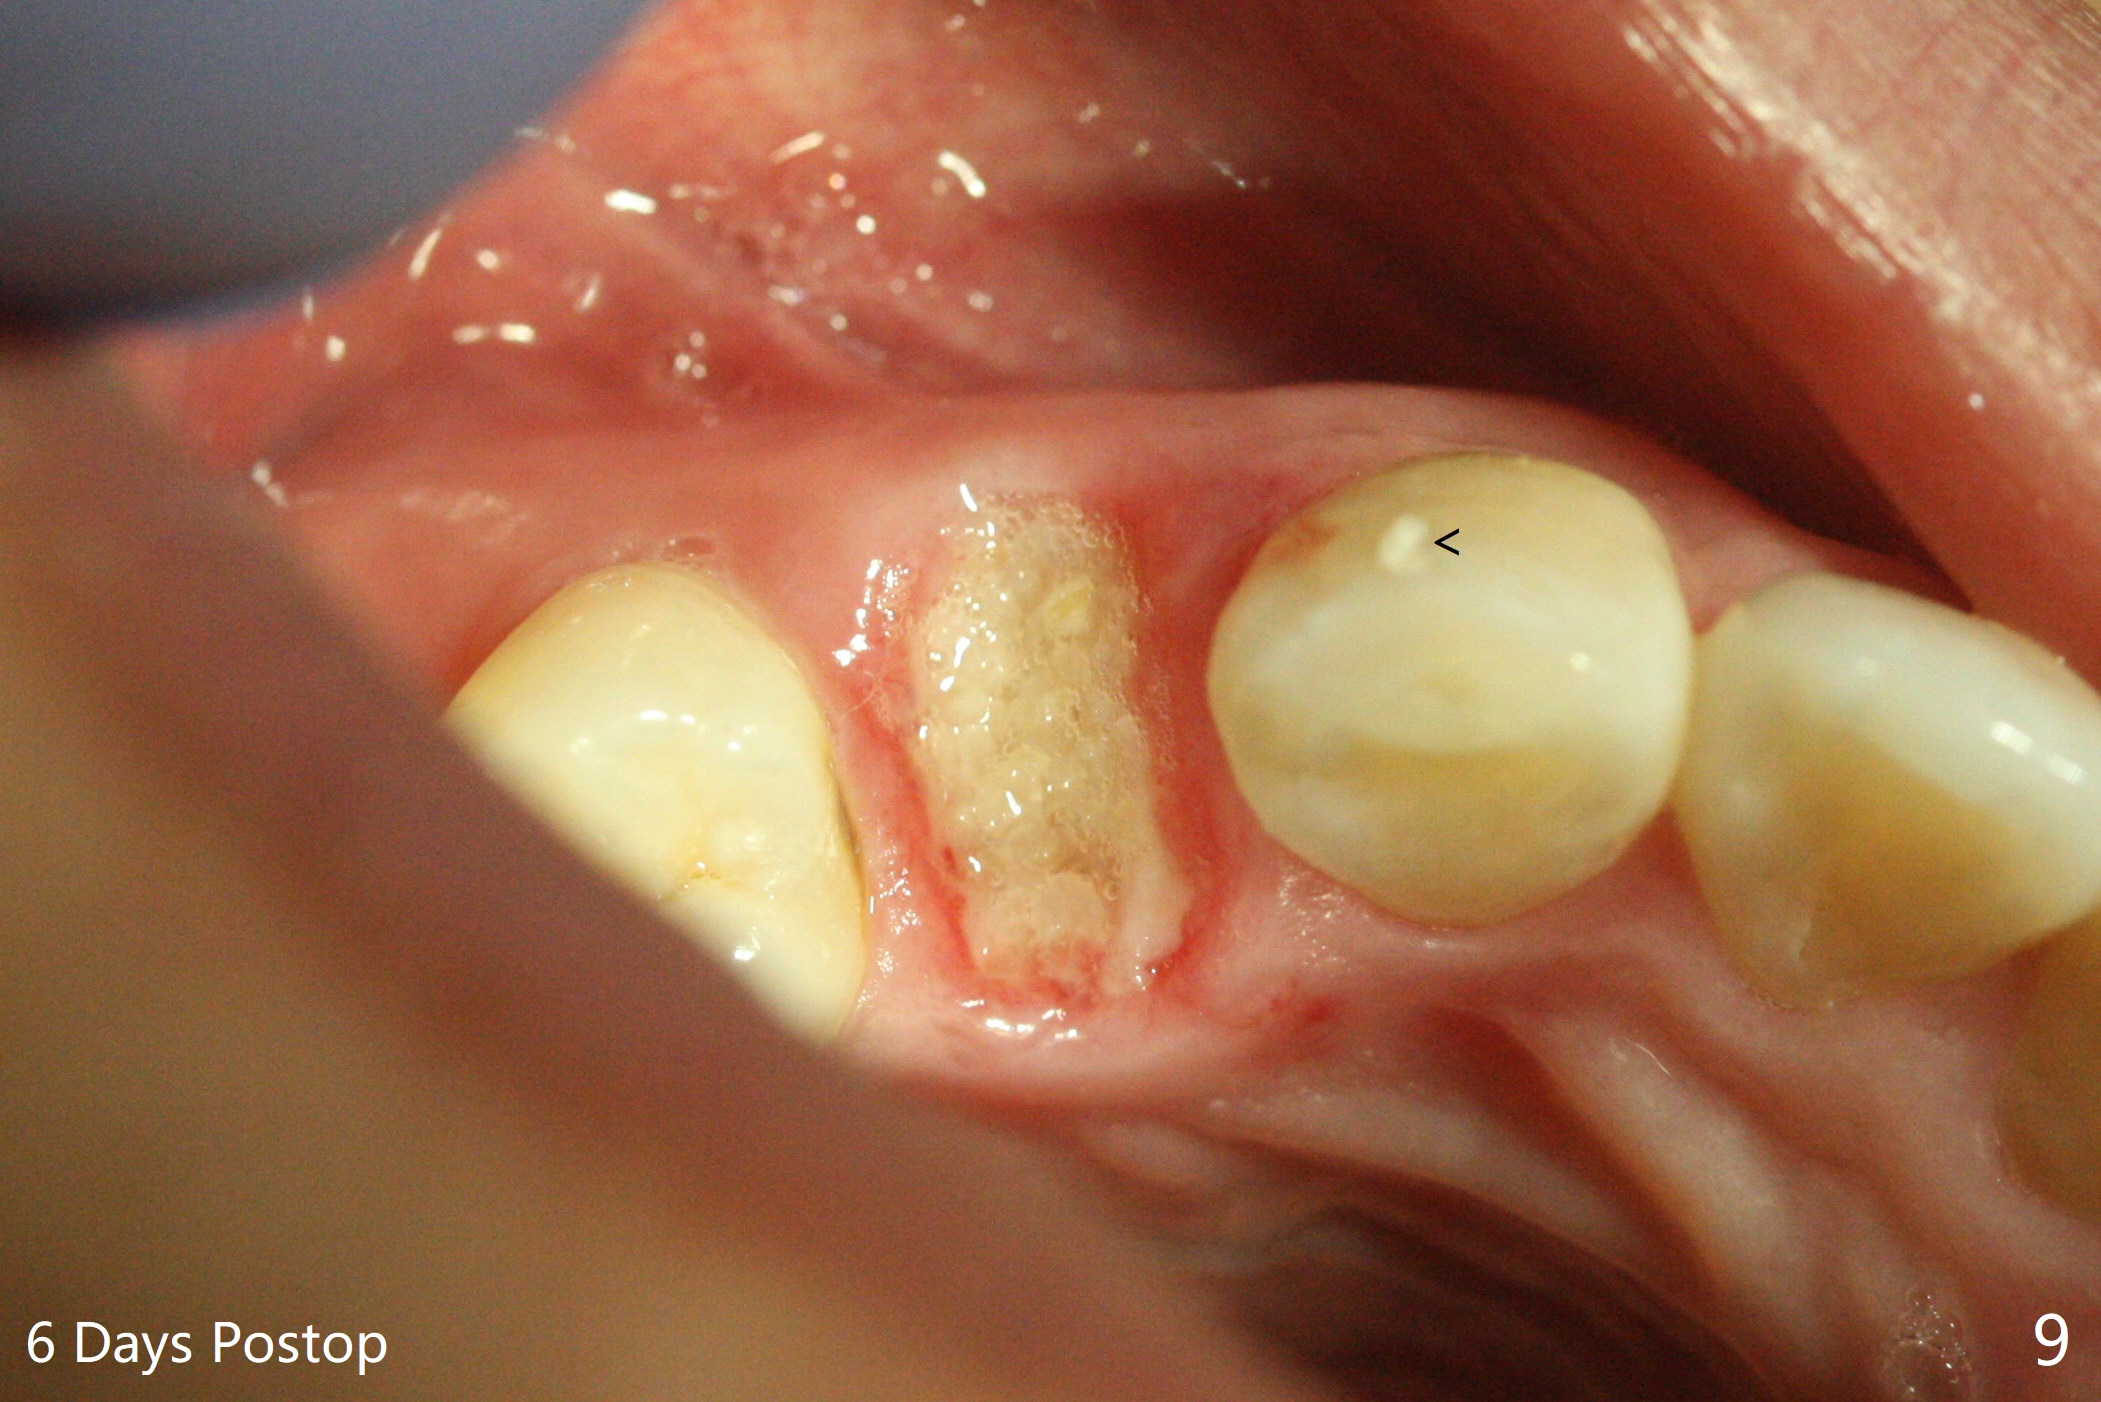

今天临床实践让我对植骨概念和操作有两方面突破,与大家分享讨论。PRF/sticky bone(粘性骨粉)以及血小板因子(成品)对软硬组织缺损修复重建无疑起到不可缺少作用。但是大多数拔牙病例并不是那么严重,放置骨粉和覆盖胶原膜足够了。为了避免费时的缝线固定胶原膜,介绍一种简易固定方法,助手可以做。31岁女不想保留严重龋坏右上4(图一至四,拍摄临床照片,与后期比较,但愿简易植骨不产生骨板塌陷),虽然术前根尖片显示根尖阴影(图四),术中没有根尖骨板缺失。估计没有严重骨板缺损,她又年轻,再生能力强,所以做简易植骨(异体骨,图五),也就是不需要PRF或者血小板因子,骨粉表面放置GEM CAP(9-12月吸收膜),由胶水固定(图六),在放置牙周敷料前,在胶原膜表面涂一层含有抗单纯疱疹病毒凡士林(图七),但愿敷料脱落时,不至于把胶原膜带下来。术后第六天,病人由于左上第二磨牙不适回来,说敷料脱落,没有不适,要求检查,其实膜也丢失(图八,九),骨粉好像挺稳定,没有做如何处理,尽管少量骨粉离开牙槽窝(<)。